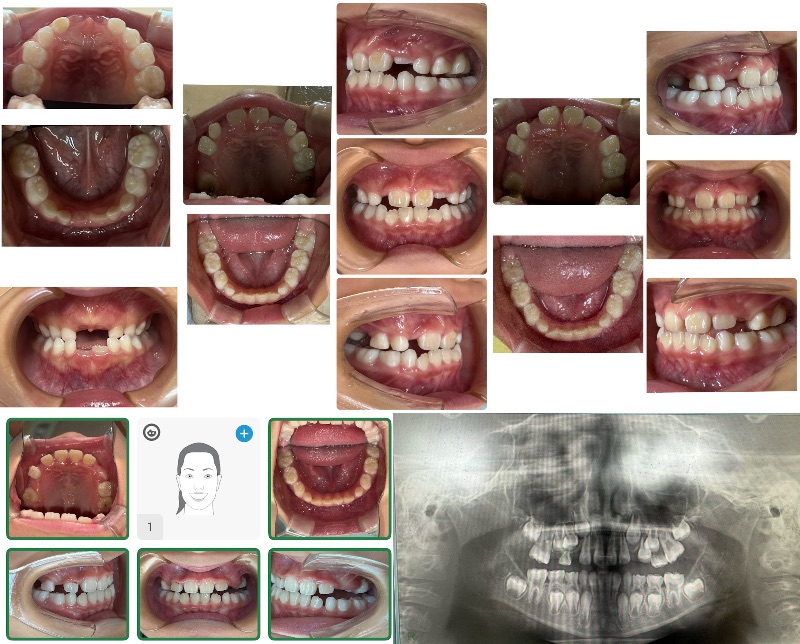

- QSmarteeステージングティーン

smartee症例のアタッチメント脱離についてご相談させてください。

Cくん 男児

現在9ステージ目使用中です。

他の症例では問題なく経過しておりますが、

本症例に限っては、

装着から約2週間で毎回ほとんどのアタッチメントが脱離している状態です。このままでは計画通りの進行が難しいと感じております。

現在の装着手順は以下の通りです。

・歯面研磨:メルサージュ使用

・エッチング(EE)、ボンディング(EB)実施

・アタッチメントテンプレート使用

・フローレジン:オムニクロマ使用なお、現在は9ステージ目まで進んでおりますが、

進捗への影響も懸念されるため、

再スキャンが必要な場合はご指示いただけますと幸いです。つきましては、以下についてご教示いただけますでしょうか。

① 小児症例特有の脱離リスク(エナメル質の性状など)の影響について

② 材料選択(オムニクロマ)の適否

③ 小児における有効な接着手技のポイント

④ 咬合干渉や生活習慣(咬み癖など)の影響の考え方本症例のみで起きている現象のため、

個別要因が強いのではないかと考えております。口腔内写真

〇アタッチメント取れなかった

×アタッチメントダツリお忙しいところ恐縮ですが、

ご教示のほどよろしくお願いいたします。 - A正規会員もしくはQAアクセス会員になると、Aが表示されます。